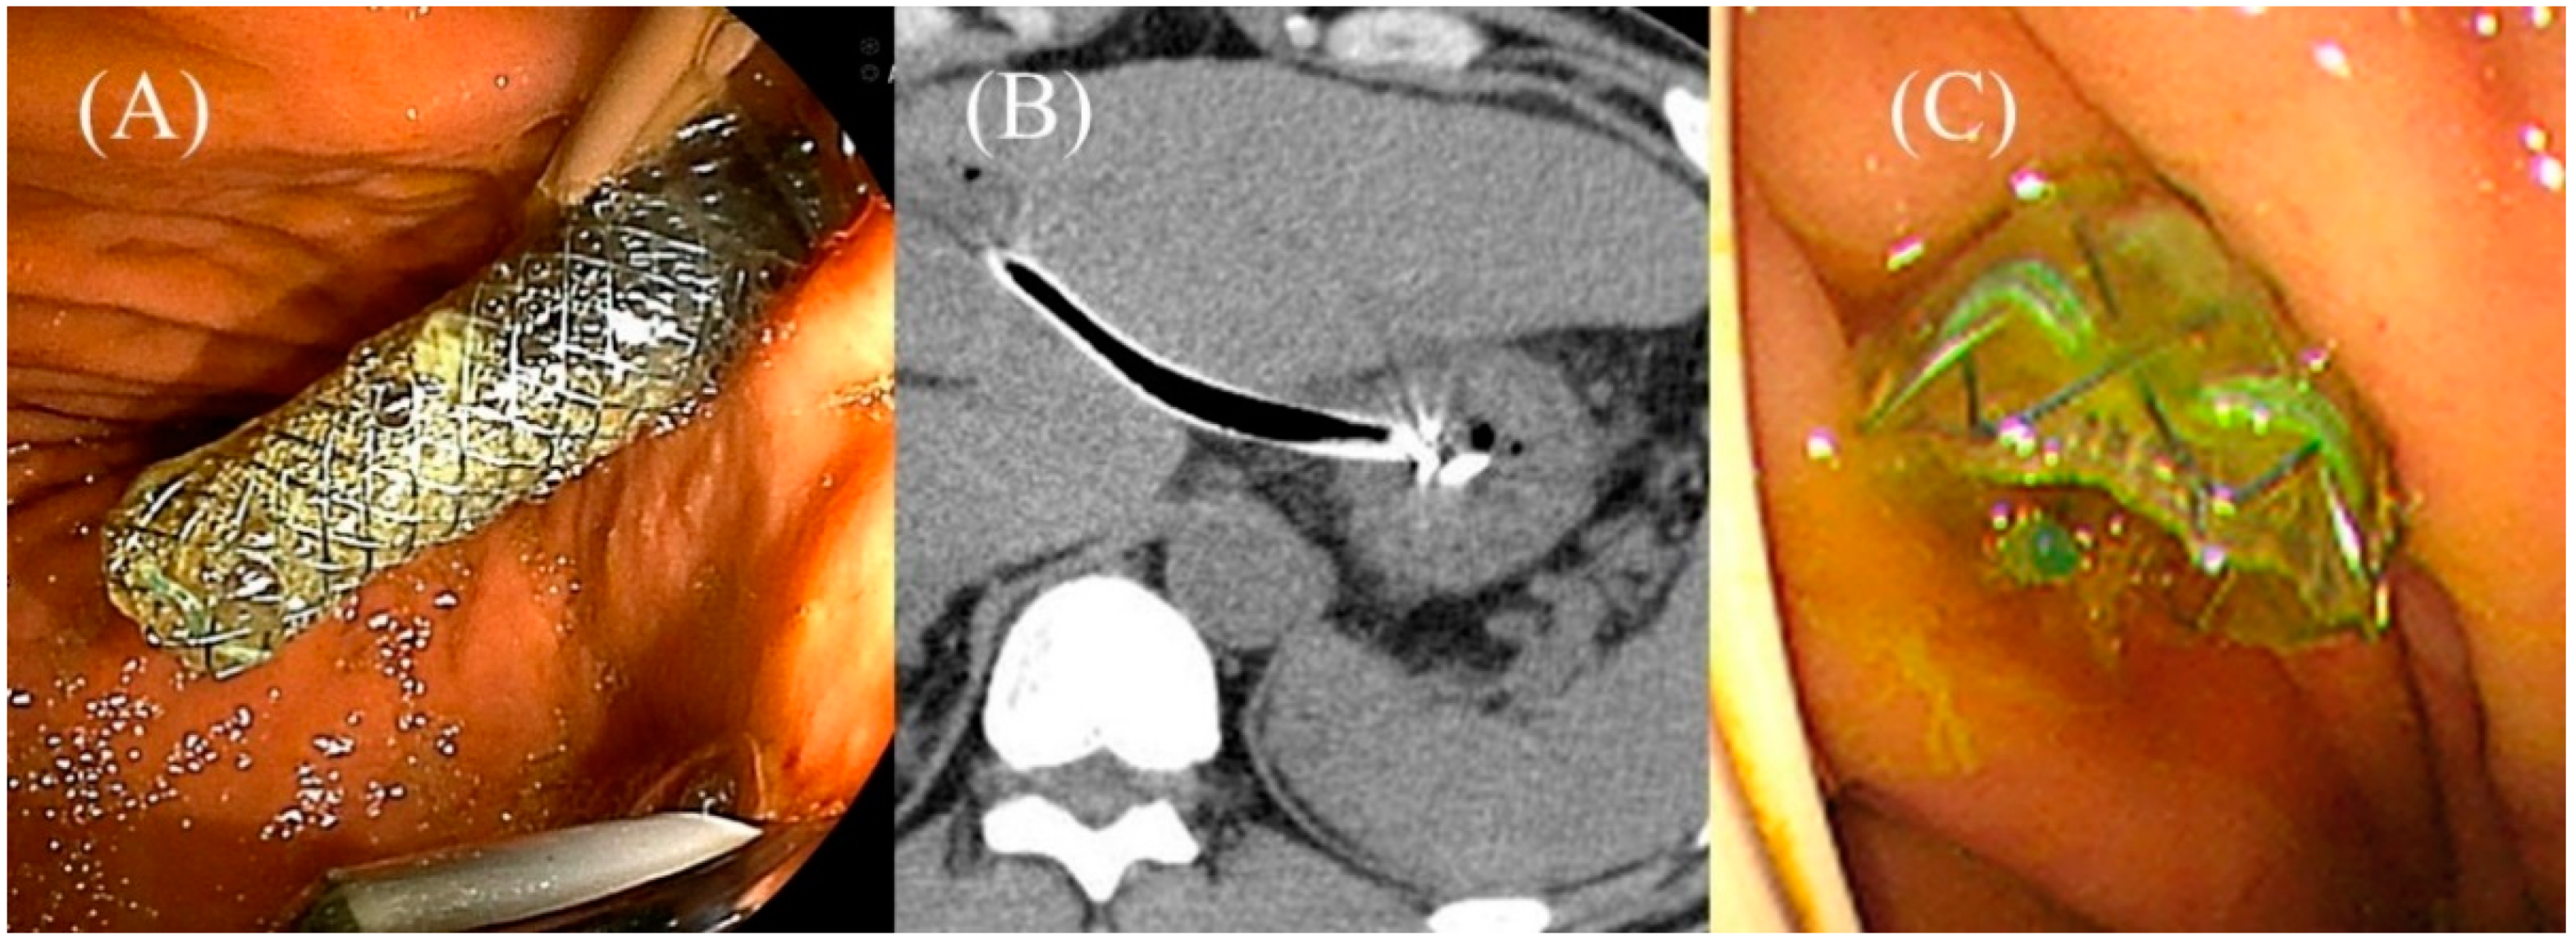

5.6. Stent Deployment